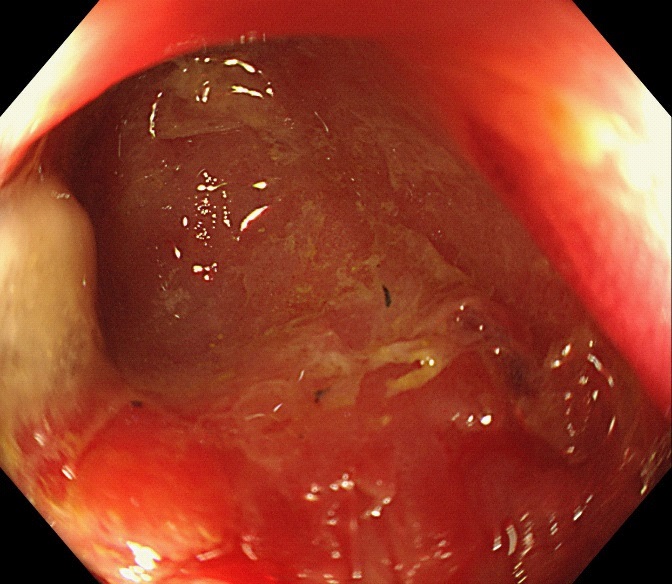

Figure 2: The computed tomography scan of abdomen showed circular high density shadow in right colon, which can be observed in colonic lumen but protruding out of the lumen.

The computed tomography scan of abdomen showed about 20 mm X 20 mm circular high density shadow in right colon, which can be observed in colonic lumen but protruding out of the lumen. Colonoscopy (Figure 3) was also performed and the fecal impaction was identified in the cecal diverticulum above the ileocecal valve. The mucosa surrounding the diverticulum was hyperemic and edema. Than the fecalith was removed successfully with a foreign forceps under colonoscopy. The internal mucosa of the diverticulum was hyperemia, and no perforation was observed (Figure 4). The patient’s abdominal pain were relieved after endoscopic treatment. To prevent recurrence of the disease, surgical removal of the diverticulum was recommended but the patient was hesitant. There was no recurrence of abdominal pain and fecal impaction during 10 months follow-up.